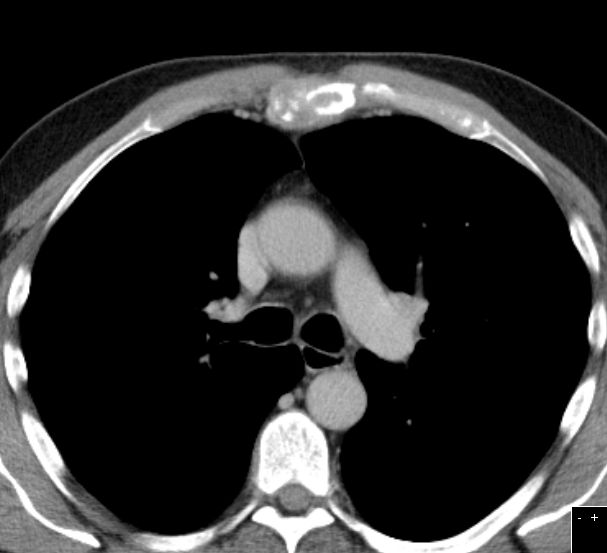

| 79-jährige Frau mit metastasiertem Nierenzellkarzinom. Destruktion der Schädelbasis links. | ||||